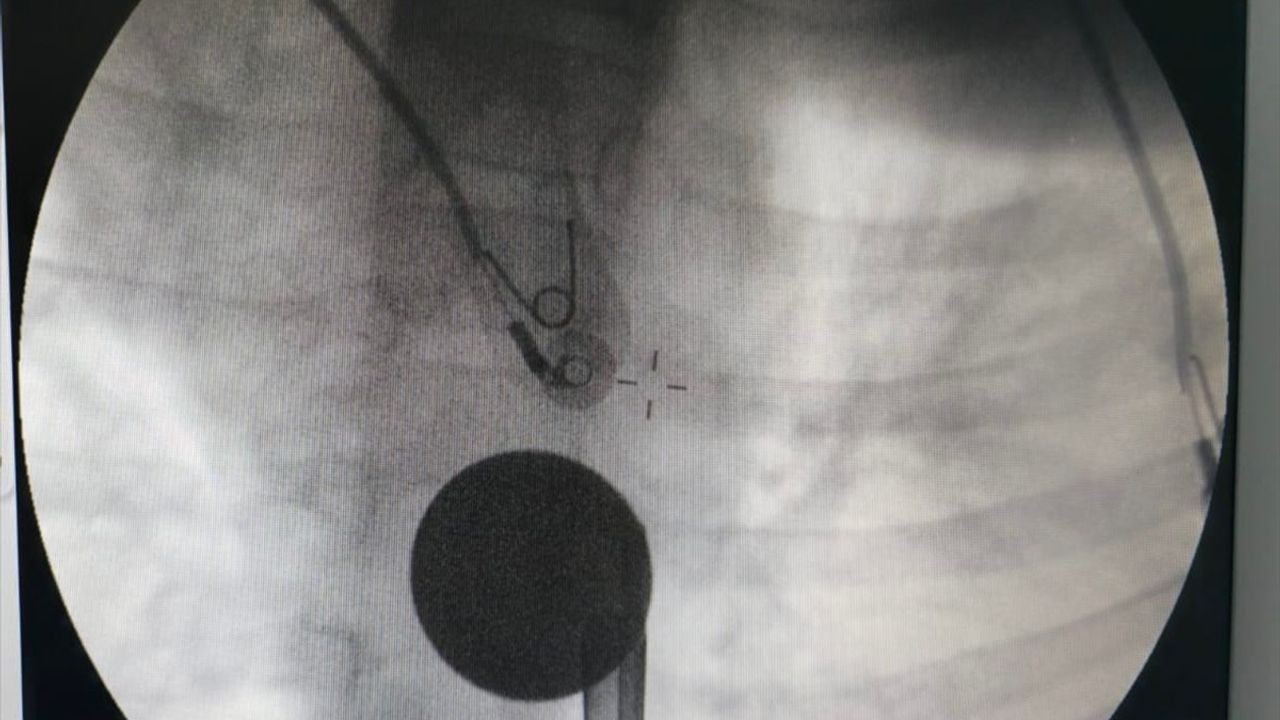

Hastanede yapılan tetkiklerde çocuğun boğazında tespit edilen madeni para, Gastroenteroloji Uzmanı Dr. Yaren Dirik ile Kulak Burun Boğaz hekimi Dr. Yasin Gökçınar tarafından yapılan operasyonla çıkarıldı.